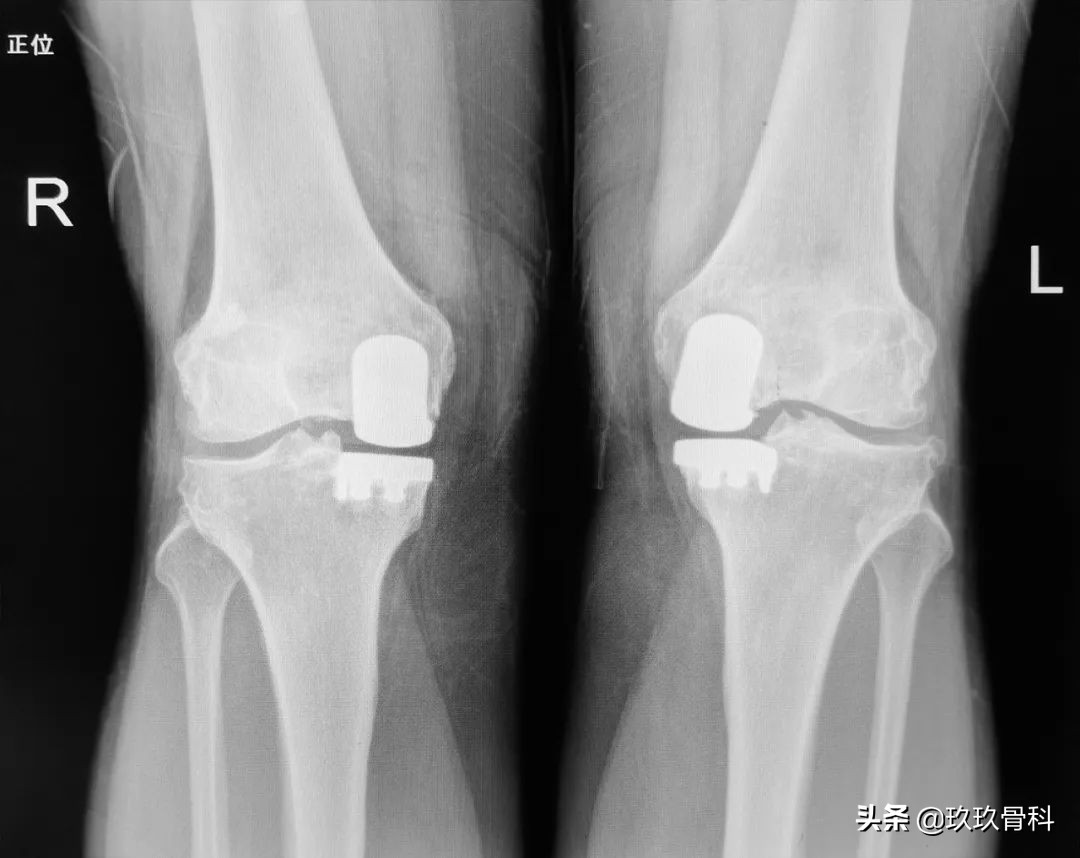

术后影像

术后第二天伸屈功能恢复良好